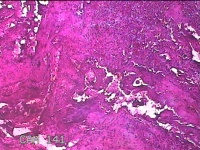

子宫左侧壁残留妊娠物

性别

女

年龄

40岁

临床诊断

稽留流产 药流失败 宫腔粘连

一般病史

停经5月余,要求终止妊娠。

标本名称

大体所见

灰白暗红色不规则碎组织1.5x1.3x0.3cm一堆,内有少许绒毛样组织。

见胎盘绒毛。

凝血中见退 变蜕膜和机化绒毛。